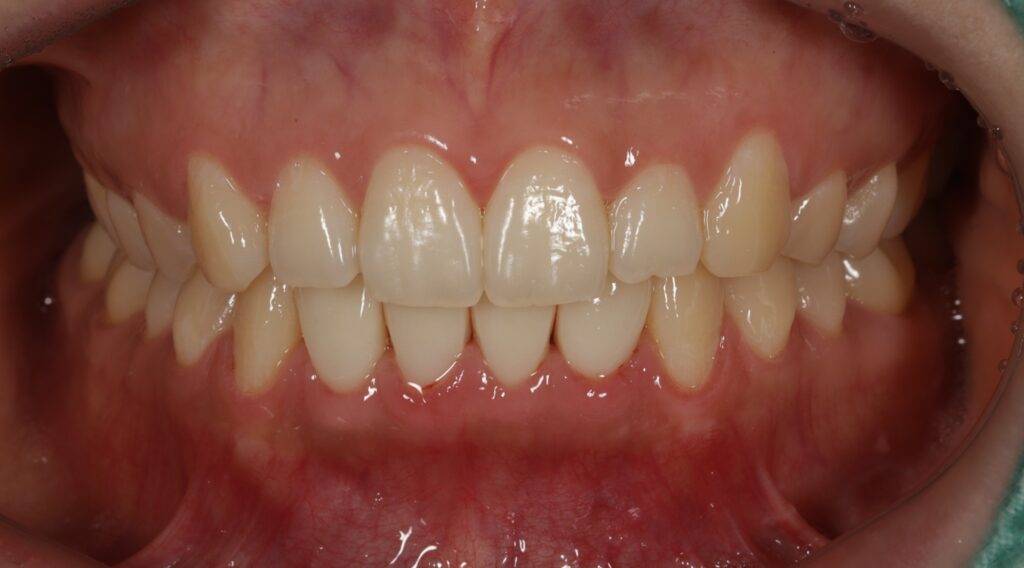

오늘은 아래 앞니 보철 치료 후

극심한 통증으로 인해 보철물을 제거하고

신경치료 후 재크라운으로 자연치아살리기를

진행하신 환자분을 소개해 드리려고 합니다.

기존 보철물의 경우 두개씩 치아를 연결해

치아 사이사이 관리가 잘 되지 않아

잇몸 반응도 좋지 않아 붉은 염증이 계속되고

있는 점도 확인하였는데요.

잇몸치료 후 회복시간을 두고 PMMA 프로비저널 크라운으로

환자분의 심미적 요구도를 확인해서

최종보철에 반영하였는데요.

빠르게 문제 없이 최종 보철까지 마무리 되어

환자분께서도 매우 만족하셨습니다.